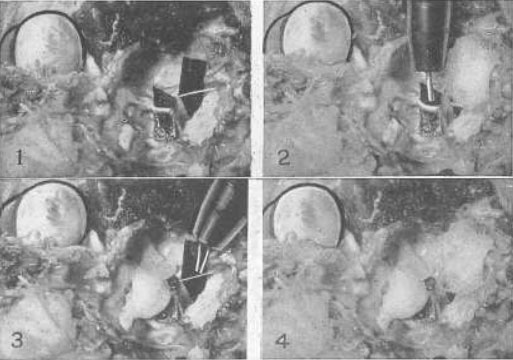

Рис. 22. Эксперимент на примере глаза кошки, демонстрирующий то, что четвертый нерв, который снабжает только верхнюю косую мышцу, является точно таким же нервом аккомодации, как и третий, и что верхняя косая мышца, которую он снабжает, есть мышца аккомодации

№ 1 – Оба нерва были выведены наружу возле их основания в головном мозге, и полоска черной бумаги была вложена позади каждого, для того чтобы изображение можно было увидеть. Четвертый нерв – это тот, что поменьше. Верхняя косая мышца была перемещена путем подгибания. Так как эта мышца всегда недоразвита у кошек, то до тех пор, пока ее натяжение не усиливают, аккомодация у этих животных не воспроизводится. Стимуляция одного или обоих нервов импульсным током способствовала возникновению аккомодации.

№ 2 – Когда четвертый нерв был покрыт ватой, пропитанной нормальным физиологическим раствором, применение импульсного тока вызвало аккомодацию. Когда вата была пропитана однопроцентным раствором атропина сульфата в нормальном физиологическом растворе, не удавалось воспроизвести аккомодацию, но стимуляция третьего нерва воспроизводила ее.

№ 3 – Когда третий нерв был покрыт ватой, пропитанной нормальным физиологическим раствором, воздействием импульсного тока была воспроизведена аккомодация. Когда вата была смочена атропина сульфатом в нормальном физиологическом растворе, то не удавалось воспроизвести аккомодацию, но стимуляция четвертого нерва аккомодацию все же вызывала.

№ 4 – Когда оба нерва были покрыты ватой, пропитанной атропина сульфатом в нормальном физиологическом растворе, применение электричества к вате не вызывало возникновения аккомодации. Когда органы были вымыты в теплом физиологическом растворе, стимуляция электрическим током каждого нерва всегда воспроизводила аккомодацию. Нервы попеременно покрывались ватой, смоченной атропином, а затем промывались теплым физиологическим раствором за один час до применения электрического тока в каждом из состояний с теми же результатами. Аккомодация никогда не могла быть воспроизведена при помощи стимуляции электрическим током, когда нервы были парализованы атропином, но всегда происходила при стимуляции каждого или обоих нервов, когда их промывали физиологическим раствором. Эксперимент был проведен с теми же результатами, что и с множеством кроликов и собаками.